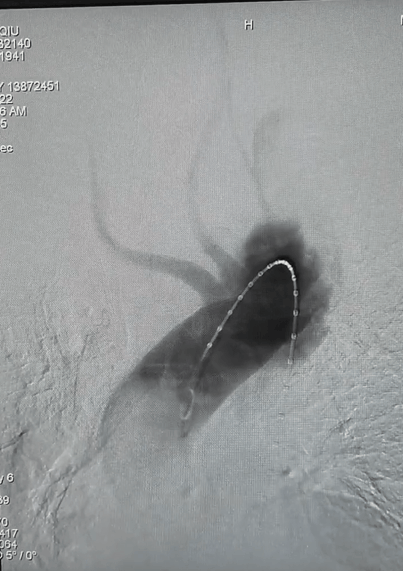

重建ARSA

按照同样的术式,将导丝超选进ARSA的内嵌分支开口后,置入Viabahn覆膜支架并释放。

超选导丝进入ARSA

ARSA释放覆膜支架